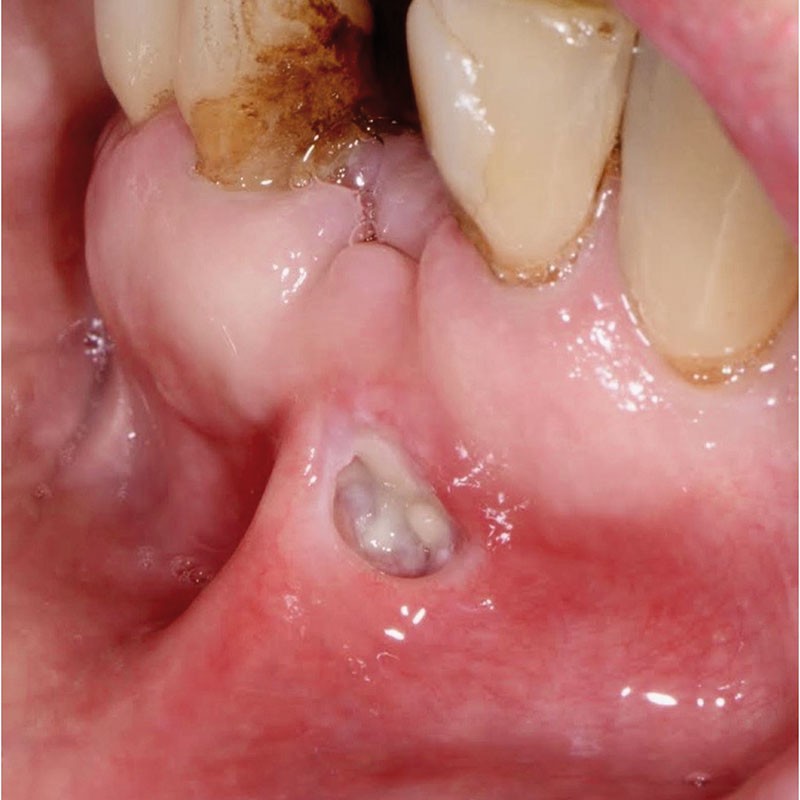

Une patiente âgée de 78 ans consulte pour une blessure qui ne cicatrise pas dans le fond du vestibule antérieur mandibulaire. La patiente est fumeuse et présente une hypertension et cholestérolémie prises en charge médicalement ; par ailleurs elle est traitée par corticothérapie (Solupred®) depuis 2 semaines pour une alvéolite due à l’extraction de 31. L’examen clinique révèle une ulcération de 1 cm de la muqueuse alvéolaire vestibulaire en regard du site extractionnel, au-delà de la ligne muco-gingivale et débordant sur le frein labial inférieur. Le fond de la lésion est nécrotique et hémorragique au contact. Les bords supérieur et médian présentent un discret remaniement kératosique réactionnel. L’ulcération est douloureuse au contact et ferme à la palpation, sans induration notable. Il existe une adénopathie sub-mandibulaire homolatérale, mobile et douloureuse à la palpation. L’examen du CBCT montre un remaniement alvéolaire post-extractionnel, sans séquestre osseux apparent.

L’hypothèse diagnostique est celle d’une ulcération associée à une ostéite post-extractionnelle. La corticothérapie inadaptée et l’absence d’antibiothérapie ont favorisé l’évolution de l’alvéolite en ostéite localisée. Le tabagisme et la traction induite par le frein labial sont des facteurs aggravants.